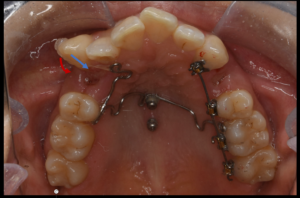

以下の動画では、抜歯によって生じたスペースに奥歯が前方へ動いてしまうのを防ぐため、アンカースクリューを使用して治療を行った症例をご紹介しています。

アンカースクリューを固定源として用いることで、奥歯の不要な前方移動(アンカーロス)を抑えつつ、目的とする歯を効率よく移動することが可能となります。

患者様は神奈川県に在住の20代女性です。前歯のでこぼこ、2番目の歯が中に引っ込んでるのを改善したいとのことで当院に来院され矯正治療を行いました。

治療として、目立たない矯正装置がいいとのことで裏側矯正とマウスピース矯正のインビザラインとを比較検討した結果、今回は裏側矯正で治療を行うこととなりました。

今回の場合だと歯を並べるスペースが不足しているため、抜歯での治療となりました。抜歯として中間の歯を上下左右で1本ずつ抜歯しました。

上顎に関しては、内に入った歯を並べるため最初は犬歯を牽引し、2番目の歯を配列できるスペースを作成後に2番目の歯を並べるので、今回の場合は一般的には治療期間が通常の4本抜歯よりも長くなることが多くなります。治療期間約3年で咬合および歯の並びが改善したため、動的治療を終了とした。